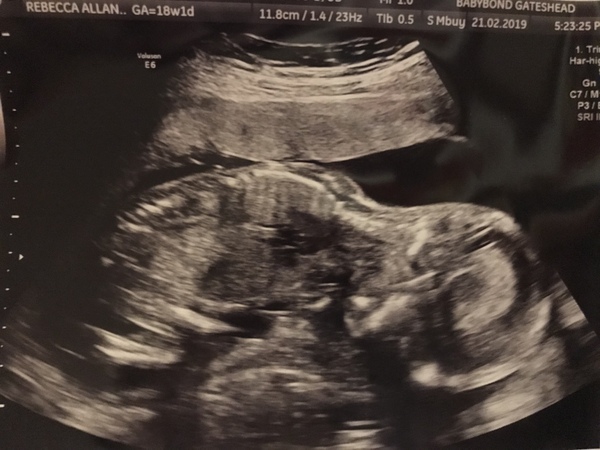

BeckyButterfly · 21/02/2019 22:32

This is as good as we got at the scan today. Face down! 😂